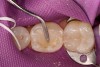

Figure 5